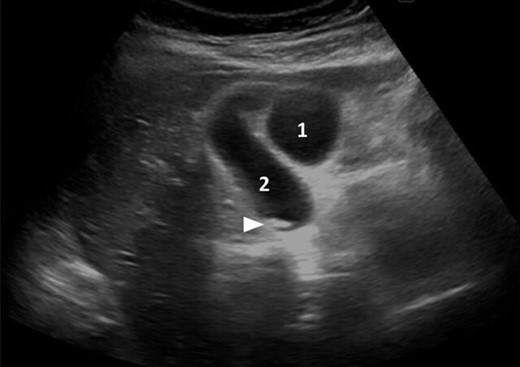

A 39-year-old healthy female, presented to our emergency department due to abdominal pain, nausea and vomiting. She was febrile, with a tender right hypochondrial and epigastric region. Her laboratory results showed a normal complete blood count and C-reactive protein level. Liver function test showed an elevation in total bilirubin at: 42 mmol/L, direct bilirubin level at: 29 mmol/L, gamma-glutamyl transferase (GGT) level at :160 U/L and Lipase level at: 34 000 U/L. An abdominal US showed two separate gallbladders with a sludge (Fig. 1). Abdominal CT scan showed a Balthazar grade C pancreatitis and confirmed the presence of a double gallbladder (Fig. 2). An MRCP confirmed the double gallbladder (Fig. 3). An ERCP was performed with evacuation of biliary debris in the common bile duct (CBD). The patient was discharged home after appropriate medical treatment a couple of days later with a full normal liver function test. Two months later, a laparoscopic cholecystectomy was performed where the two gallbladders were dissected with a dome-down technique, from the gallbladder fundus towards the neck (Fig. 4), the cystic duct and artery were identified. An intraoperative cholangiography was performed which showed patent intrahepatic ducts, cystic and CBD (Fig. 5). A Hem-o-lock® clip (WECK Closure System; Teleflex Inc., Morrisville, NC, USA) was then placed on the main cystic duct (Fig. 6), and another Hem-o-lock® clip was placed on the cystic artery. Figure 7 showing the gross specimen. The final histopathology report concluded two separate gallbladders, each having its own cystic duct, with both cystic ducts joining to form a main cystic duct.

Ultrasonography showing the two distinct gallbladders (1 and 2) with sludge in one of them (arrowhead).